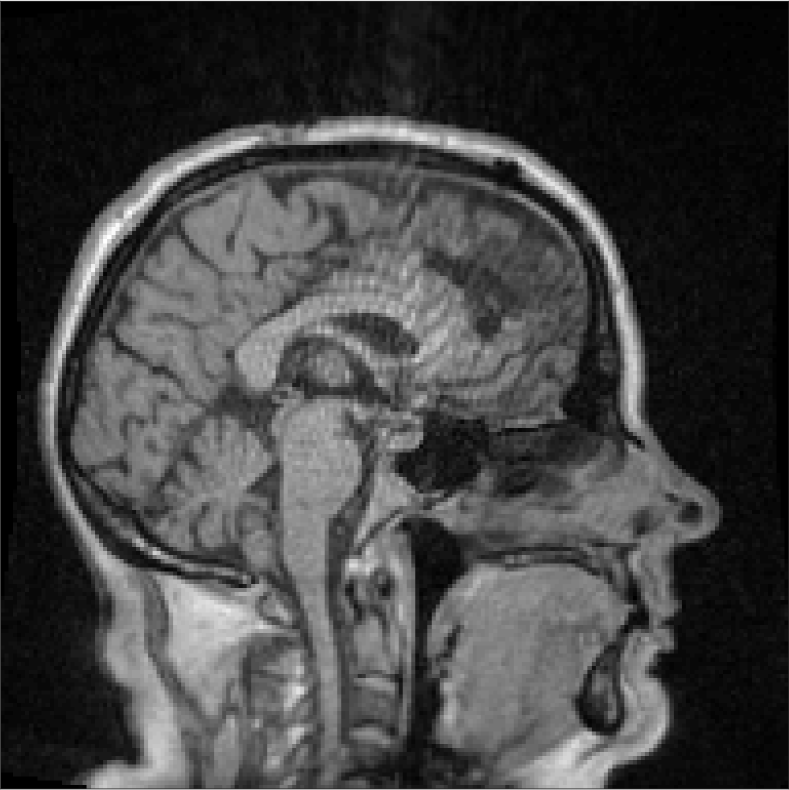

All MR images were acquired with a 1.5 T Siemens Espree scanner. The UTE images were reconstructed to 192×192×192192192192192\times 192\times 192 voxel bitmapped images with an isotropic resolution and a voxel size of 1.33 mm. The UTE sequences sampled the k-space radially with 30 000 radial spokes. CT images were acquired with a tube voltage of between 120 kV and 130 kV on either a GE Lightspeed Plus, Siemens Emotion 6 or GE Discovery 690. The in-plane pixel size varied between 0.48 mm to 1.36 mm and the slice thickness between 2.5 mm and 3.75 mm. Images of the same patient were co-registered and resampled to achieve voxel-wise correspondence between all five modes. A binary mask excluding most of the air surrounding the head was computed from the images and used to remove unnecessary data. Furthermore, to reduce the execution time of the parameter estimation phase, only 11 slices in the middle of the head of each patient was used during the parameter estimation phase, but all slices were used during the prediction phase (s-CT generation). Additional details concerning the data can be found in Johansson et al. [16]. Data from one slice of a patient is shown in Figure 3.

Refer to caption

(a) Binary mask

(b) CT

(c) First echo, 10superscript1010^{\circ}

(d) Second echo, 10superscript1010^{\circ}

(e) First echo, 30superscript3030^{\circ}

(f) Second echo, 30superscript3030^{\circ}

Figure 3: Binary data mask (panel a), CT image (panel b), The four MRI UTE sequences (panels c-f).